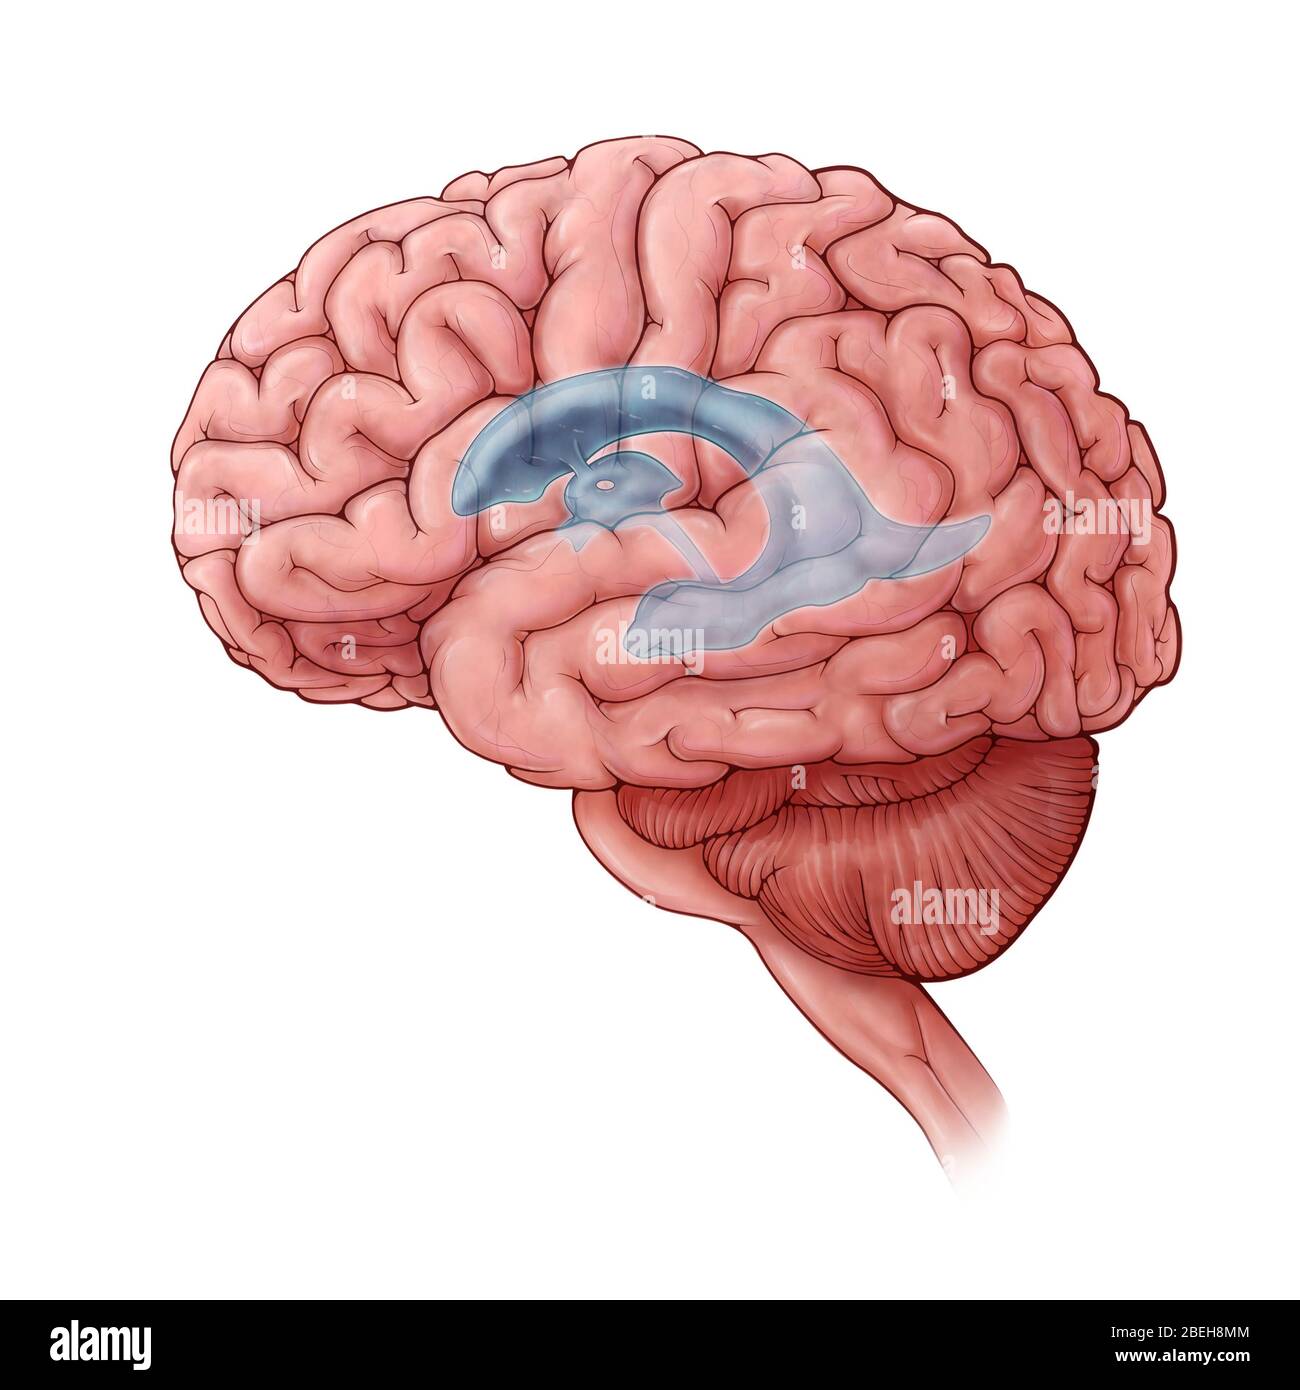

RF3CN8WHW–Darstellung der vergrößerten lateralen und dritten Ventrikel des Gehirns (Hydrozephalus), hervorgerufen durch einen Hirntumor, der den Aquädukt des Gehirns komprimiert.

RF3CN8WHP–Illustration des vergrößerten lateralen und dritten Ventrikels des Gehirns (Hydrozephalus), hervorgerufen durch einen Hirntumor, der den Aquädukt des Gehirns komprimiert.

RF3CPM9D2–Darstellung der vergrößerten lateralen und dritten Ventrikel des Gehirns (Hydrozephalus), hervorgerufen durch einen Hirntumor, der den Aquädukt des Gehirns komprimiert.

RF3CPM9D7–Darstellung der vergrößerten lateralen und dritten Ventrikel des Gehirns (Hydrozephalus), hervorgerufen durch einen Hirntumor, der den Aquädukt des Gehirns komprimiert.

RF3CPM9DA–Darstellung der vergrößerten lateralen und dritten Ventrikel des Gehirns (Hydrozephalus), hervorgerufen durch einen Hirntumor, der den Aquädukt des Gehirns komprimiert.

RF3CPM9D6–Darstellung der vergrößerten lateralen und dritten Ventrikel des Gehirns (Hydrozephalus), hervorgerufen durch einen Hirntumor, der den Aquädukt des Gehirns komprimiert.